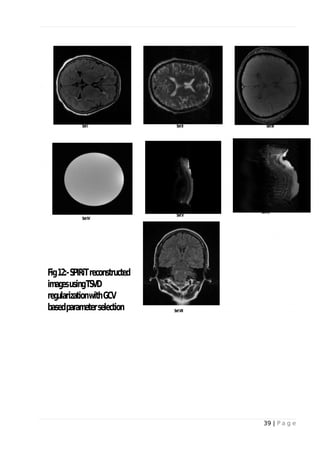

Fig-11 and Fig-15 shows the GCV values plotted as a function of the truncation parameter. The

optimum parameter is indicated using asterisk (*). It is evidently clear that optimum parameter

values are higher than L-curve. The reconstructed images are show in Fig-12 and Fig-16. Data set

V shows significant amount of aliasing and data set VI shows quiet amount of noise.

Fig 12: - SPIRiT reconstructed images using TSVD regularization with GCV based

parameter selection